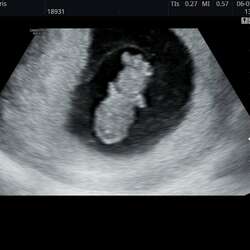

Hier eerste ronde met letrozol en meteen zwanger. Helaas miskraam gehad op 7 weken😔